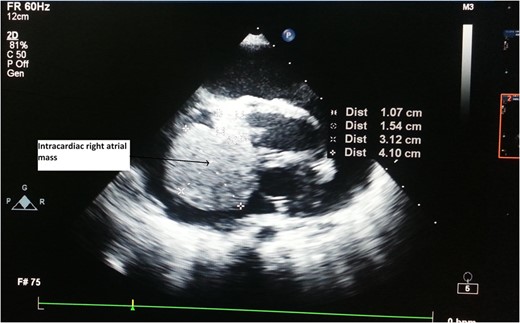

CT Thorax showing intracardiac right atrial mass with extracardiac extension.

Serum markers on day of surgery were Alpha Feto Protein (AFP) 131 146 ng/ml (normal range 0–20 ng/ml), Beta subunit of Human Chorionic Gonadotropin (beta hCG) 0.5 mIU/ml (normal range < 2 mIU/ml), Lactate Dehydrogenase (LDH) 1231 U/L (normal range 0–850 U/L)

Serum markers, histopathological examination and IHC all three confirmed diagnosis of yolk sac tumour.